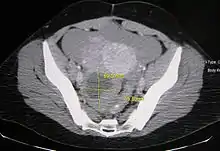

غالباً ما يتمّ تشخيص سرطان المبيض إما عن طريق الأشعة فوق الصّوتيّة، أو الأشعة المقطعيّة، أو الرنين المغناطيسي، وتكون مرتبطة بأعراض إكلينيكية وفحوصات الغدد الصمَاء تكون ضرورية بحسب الحالة.

ليس من الضروري متابعة المريضات في سن الإنجاب مستقبلاً عن طريق الأشعة فوق الصوتية للتحرّي عن التكيّسات البسيطة الاقل من 5 سم؛ لأن هذه التكيسات تكون عادة جريبات بويضية طبيعية. وتتطلب التكيسات البويضة البسيطة الأكبر من 5 سم والاقل من 7 سم في السيدات ما قبل سن اليأس المتابعة السنوية. التكيسات البسيطة الأكبر من 7 سم لا يمكن تقييمها باستخدام الأشعة فوق الصوتية لحجمها الكبير، ولذلك فهي تتطلب تصوير بالرنين المغناطيسي أو تقييم جراحي. مصدر القلق الوحيد للتكيّسات الكبيرة هو احتماليّة عدم القدرة على رؤية الأنسجة الرخوة العقيدية أو الحواجز الغليظة في الجزء الخلفي من جدارها وذلك بسبب عدم قدرة الأشعة الفوق الصوتية على اختراقها. بالنسبة للجسيم الأصفر وهو الجسيم السائد المسؤول عن التبويض الجريبي ويظهر عادةً ككيس مُحاط بجدران غليظة وذا حدود داخلية، فالمتابعة ليست ضرورية إذا كان قطر التكيَس أقل من 3 سم. تتطلب التكيّسات البسيطة الأكبر من 1 سم وأقل من 7 سم في السّيدات بعد سنّ اليأس المتابعة السنويّة، بينما تحتاج التكيّسات الأكبر من 7 سم لاستخدام أشعة الرنين المغناطيسي أو التقييم الجراحي.